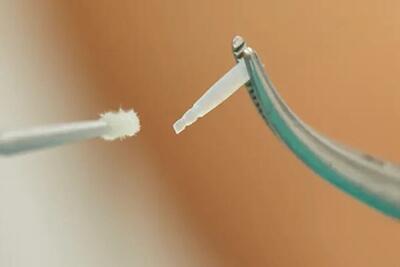

عصب کشی دندان

عصب کشی دندان چگونه است؟

عصب کشی دندان چیست؟ هرآنچه باید قبل از نشستن روی صندلی دندانپزشک بدانید

تا چند روز بعد از عصب کشی دندان درد دارد

تا چند روز بعد از عصب کشی دندان درد دارد

عصبکشی: راهی برای ترمیم ساختار دندان

در این مقاله، به بررسی فرآیند عصبکشی میپردازیم تا شما را با اهمیت و روشهای این رویکرد پزشکی آشنا کنیم. همراه ما باشید تا به دنیایی از سلامت و لبخند زیبا سفر کنیم.